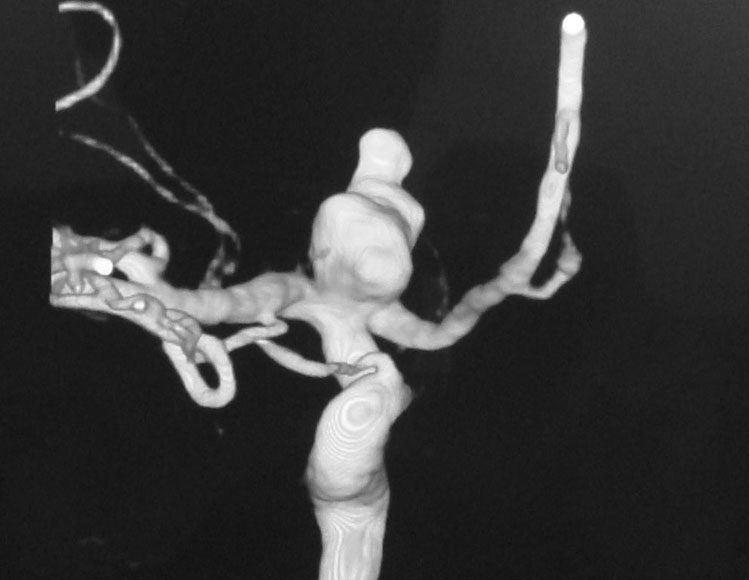

ICA Bifurcation Aneurysm

A 38-year-old-male was admitted with sudden onset of severe global headache and vomiting, followed by altereation in sensorium. CT brain showed subarachnoid and intraventricular hemorrhage (Fig 1). MRI brain revealed deep seated right sided thalamic hematoma due to ruptured internal carotid artery bifurcation aneurysm (Fig 2), confirmed by cerebral digital subtraction angiography (Fig 3). He underwent clipping of the aneurysm by transciliary supraorbital keyhole minicraniotomy (see video). Postoperative angiography showed complete occlusion of the aneurysm (Fig 4). When discharged ten days later, there was no neurological deficit (Fig 5).

Fig 4

(Fig 4)